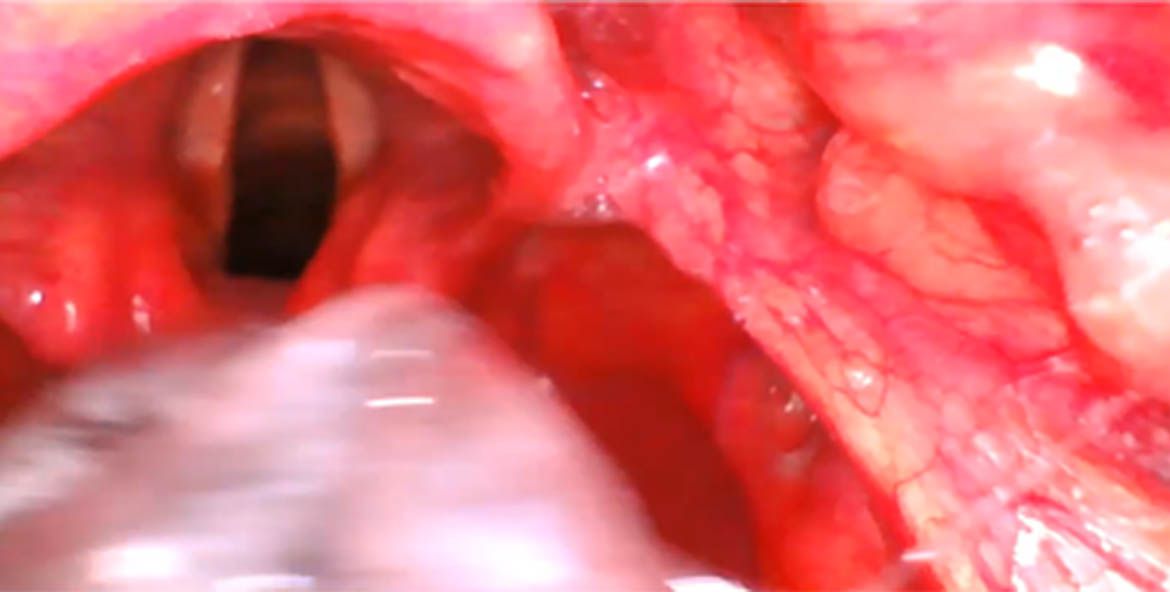

Una de las cosas que frecuentemente nos preguntamos y que a veces es una causa muy común de cuando utilizamos inicialmente los videolaringoscopios ¿por que a veces yo no puedo intubar' y les voy a presentar una serie de imágenes, en el que ustedes alcanzan a ver que tiene un perfecto cormac uno pero que al momento que ustedes introducen el tubo no lo pueden meter a las cuerdas vocales y esto porque puede ser pues por varias cosas.

2- introducimos muy profundo y aquí lo vemos en esta imagen (1) que inclusive se ve en la parte inferior el esófago y yo veo aquí las los cartílagos aritenoides y que si yo introduzco el tubo en esa forma pues irremediablemente me voy a ir a el esófago. Pero lo puedo corregir y una de las formas de corregirlo es liberar un poquito esa imagen retirar un poco y redirigir el tubo y con esta maniobra pues tenemos mucho

más éxito.

3-Choque con aritenoides Cuando yo quiero introducir el tubo y choca muy frecuente con el cartílago aritenoides éste es por lo mismo porque a lo mejor la introducción es muy profunda porque el tubo no lo monte bien en una guía o porque simplemente con el hecho de retirarse un poquito de redirigirte es la forma en la que vas a poder realizar y tener un éxito en tu intubación